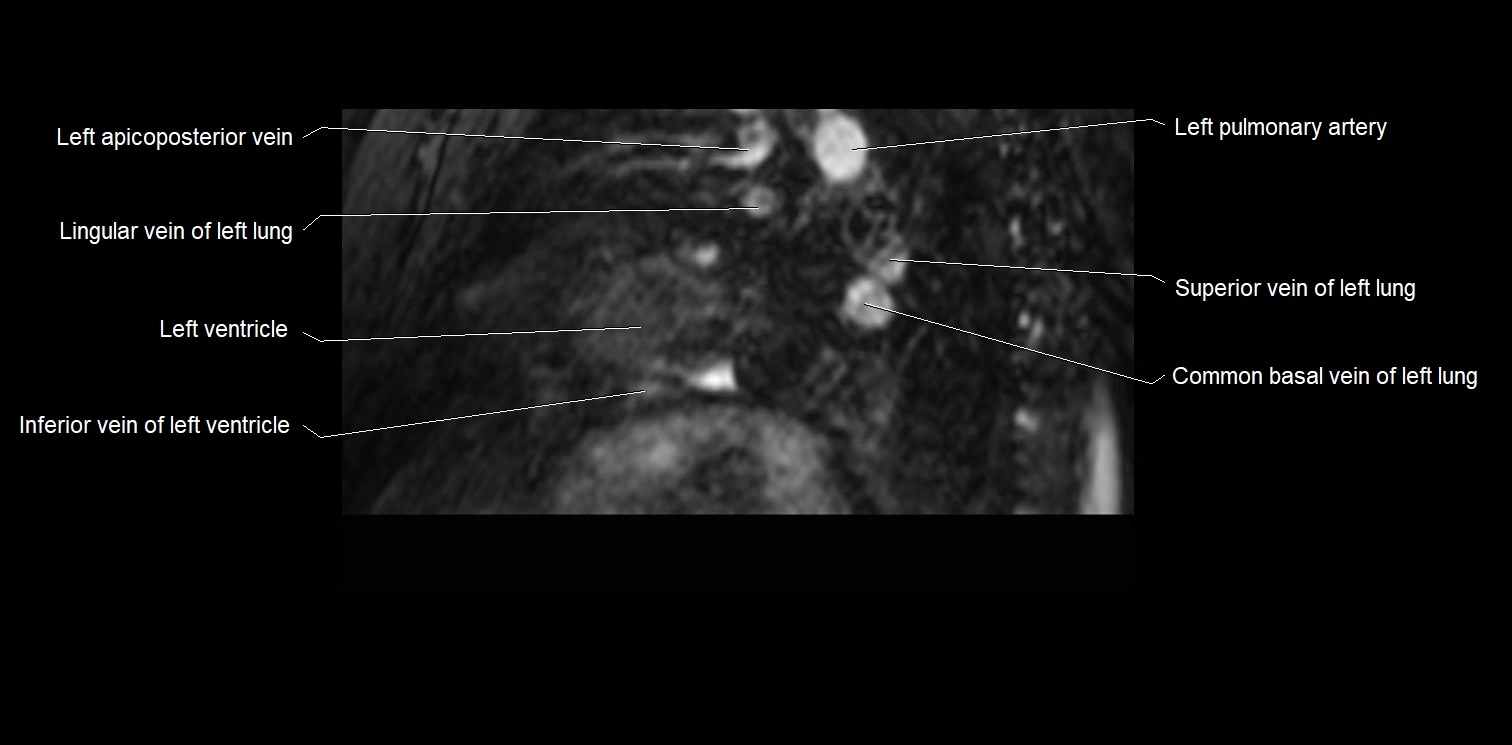

MRI image